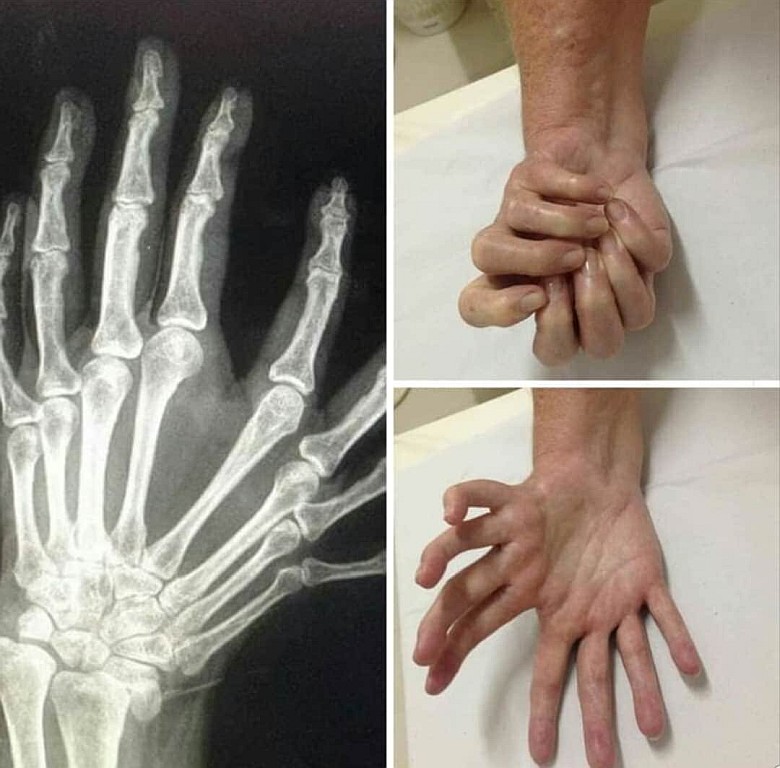

Syndrom ręki zwierciadlanej